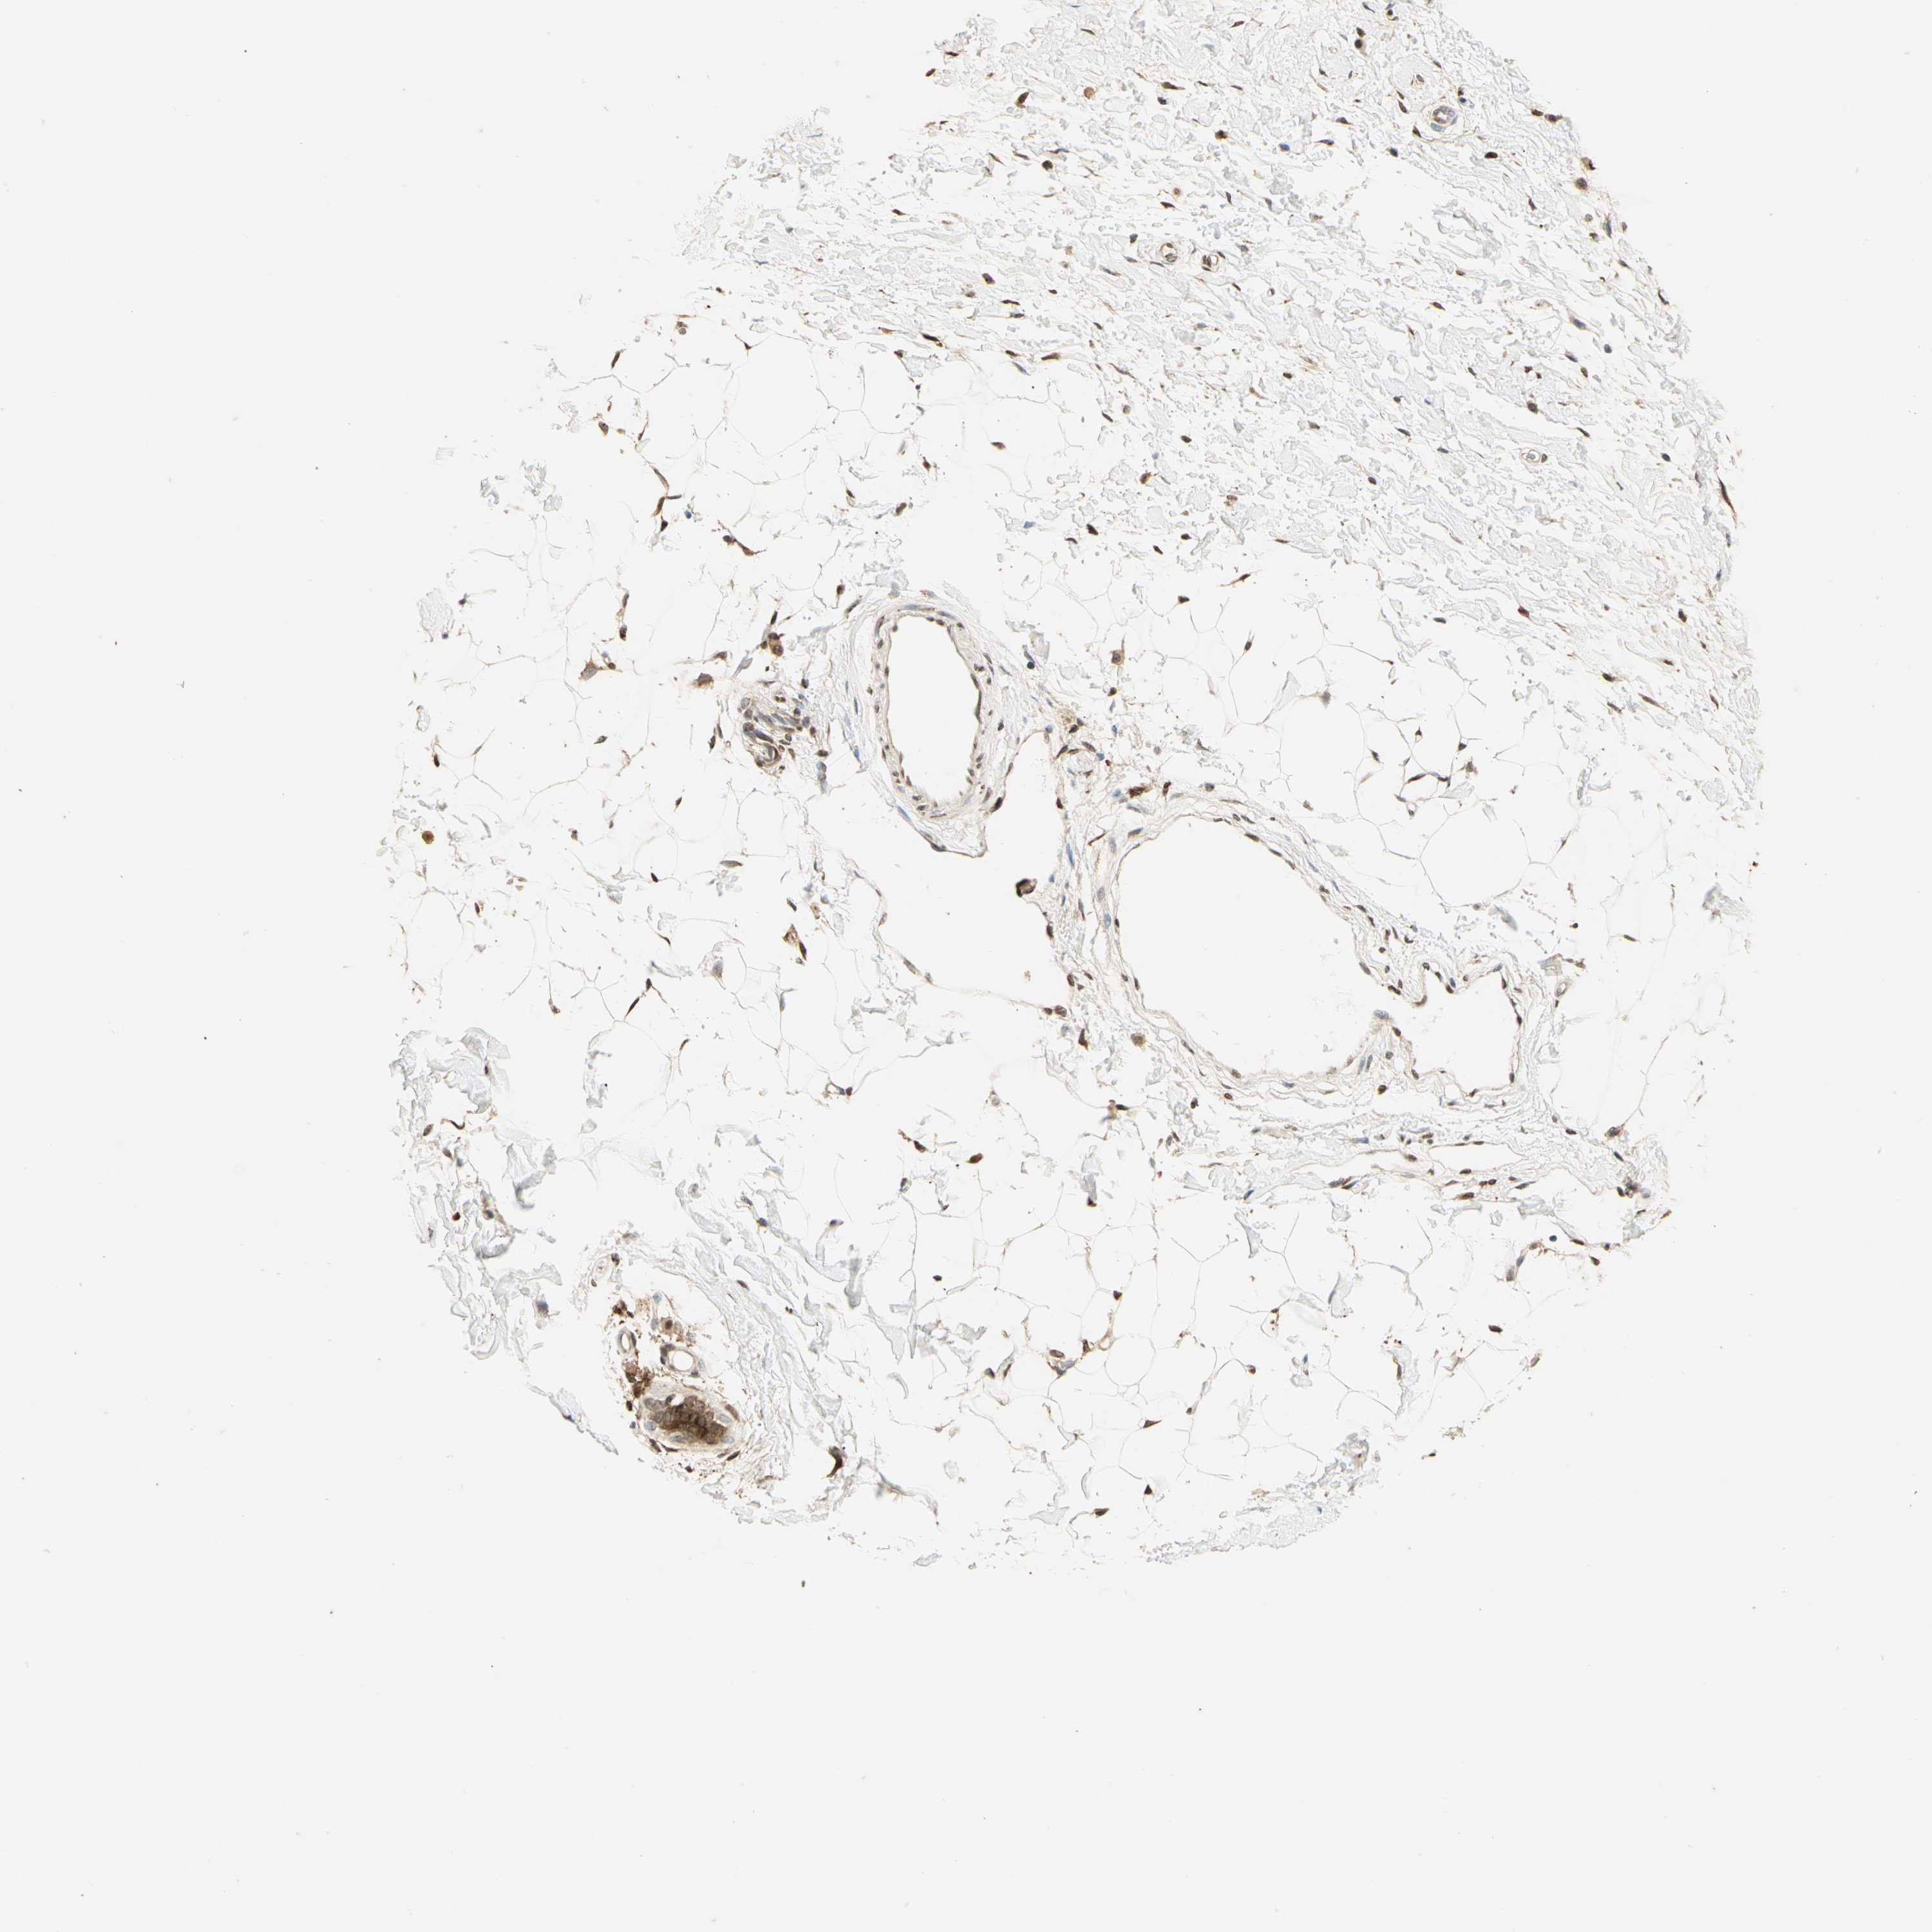

CANCER BREAST CANCER Show tissue menu

BRCA TCGA BRCA VALIDATION PROTEIN EXPRESSION

ANTIBODIES

AND

VALIDATION